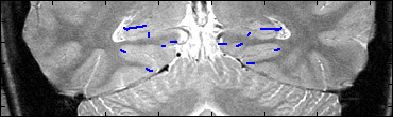

This is an example of one subjects demarcation. The A/P slice is slice

3.